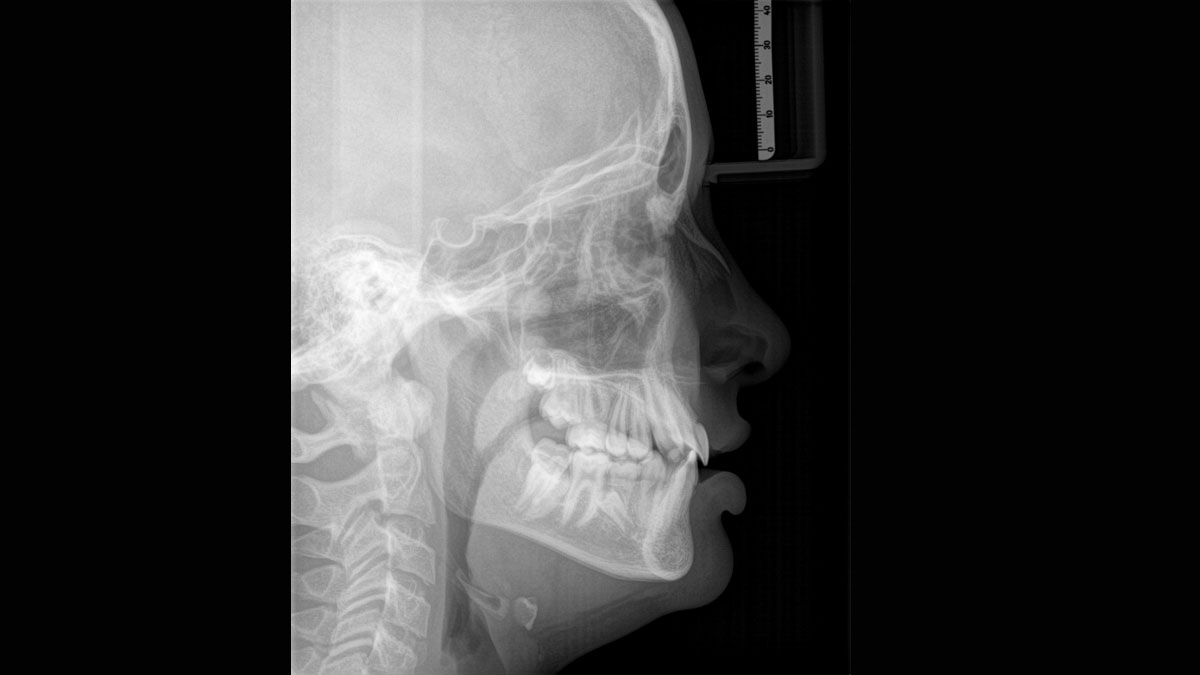

Para obtener imágenes panorámicas excepcionales con alta nitidez. Puede elegir un brazo cefalométrico derecho o izquierdo opcional, que puede reacondicionarse en cualquier momento

El sensor de conversión directa (Direct Conversion Sensor, DCS) ha revolucionado el estándar de la imagen panorámica. Las imágenes radiológicas se convierten directamente en señales eléctricas. Por lo tanto, no hay pérdida de señal debido a conversión de la luz, como es el caso de los sistemas convencionales. El resultado: imágenes con un alto nivel de nitidez y contraste, incluso con una dosis de radiación extremadamente baja. Para obtener información de diagnóstico precisa a fin de apoyar el tratamiento objetivo.

El enfoque correcto es crucial para excelentes radiografías panorámicas. Con la función de autofoco, usted recibirá automáticamente una imagen con la mejor nitidez posible en foco. Los dispositivos de radiología de Dentsply Sirona toman varios miles de imágenes individuales en un ciclo e identifican automáticamente las áreas donde la mandíbula está posicionada de manera óptima. Luego, sin ningún paso manual adicional, estas imágenes se muestran en una nítida imagen final.